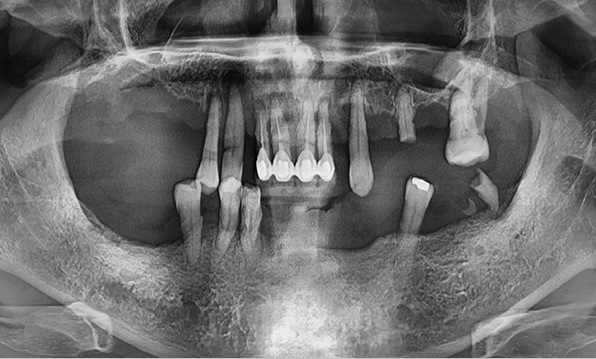

3D 디지털 진단을 통한 체계적인 계획

전체 임플란트는 위턱과 아래턱의 교합, 잇몸뼈의 상태 및

얼굴 변화 등 모든 것을 고려해 식립해야 합니다.

서울더자연치과는 3D 디지털 기술의 정밀 진단을 바탕으로

수술 계획을 세워 수술을 집도합니다.

치료기간 : 2021.04.12~2021.09.15